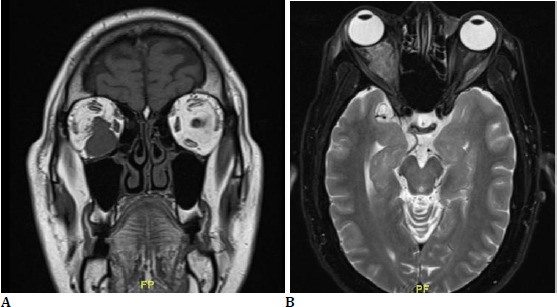

Hidradenocarcinoma is a rare form of malignant adnexal tumor. This malignant tumor has been reported to metastasize to regional lymph nodes, and distant metastasis into structures like the orbit and extraocular muscle is uncommon. Orbital metastasis comprises about 10% of all orbital neoplasms. Common systemic malignancies contributing to orbital metastasis are breast cancer, prostate cancer, and skin malignancy, melanoma. We report the case of a middle-aged man with left axillary hidradenocarcinoma with an orbital metastatic lesion infiltrating the inferior rectus muscle with optic nerve involvement. This case report describes a rare presentation of orbital metastasis from an adnexal tumour.